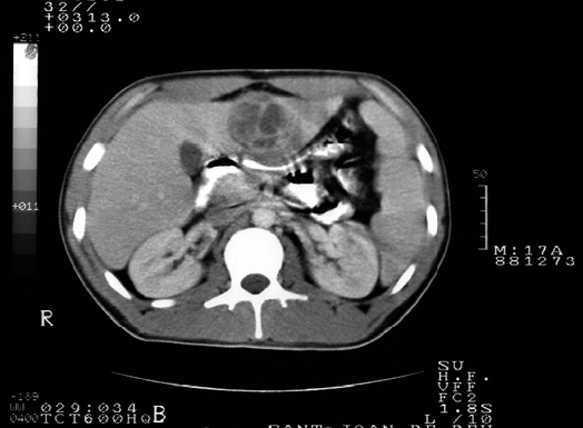

Paciente varón de 17 años con fiebre y dolor abdominal hace 8 días, vómitos y diarreas. Deportista de élite sin antecedentes. No refiere traumatismo, ingesta de productos lácteos no pasteurizados ni viajes exóticos. Presenta un excelente estado general y dolor abdominal generalizado, sin masas, visceromegalias ni signos de irritación peritoneal. Se realizan determinaciones analíticas (leucocitos 13.400 μl; 74 %, neutrófilos segmentados; 6 %, neutrófilos bandas; proteína C reactiva, 19,6 mg/dl; función renal y hepática normales) y hemocultivos seriados. La radiografía de tórax y abdomen y el sedimento de orina son normales. Tras 48 h persiste febril, con dolor en el epigastrio. Con sospecha de enfermedad biliar se solicita una ecografía abdominal que muestra imagen quística en lóbulo hepático izquierdo compatible con absceso piógeno, y se confirma por TC abdominal (fig. 1). Se realiza punción-aspiración con aguja fina (PAAF) obteniendo 45 ml de líquido purulento. Se inicia tratamiento con piperacilina-tazobactam y metronidazol quedando afebril a las 48 h. En la muestra crece un microorganismo anaerobio que no es posible identificar. Los hemocultivos y las serologías (Entamoeba histolytica, Toxocara, Equinococcus granulosus y Bartonella henselae) son negativos. El estudio inmunitario básico (inmunoglobulinas totales y subclases y poblaciones linfocitarias) normal no sugiere síndrome de Papillon-Léfèvre, a pesar de constatarse periodontitis. Tras 3 semanas de antibioterapia presentó un pico febril (38 °C) y exantema cutáneo con neutropenia grave (neutrófilos absolutos 84/μl, serie roja y plaquetaria normal) de posible origen medicamentoso. Se suspenden los antibióticos utilizados y el metamizol, iniciándose meropenem. La punción medular muestra hiperplasia con detención de la serie blanca en fase de mielocitos/metamielocitos y eosinofilia. Se administró factor estimulador de colonias granulocíticas, recuperándose el recuento de neutrófilos. Tras 4 semanas de antibioterapia intravenosa se da el alta con pauta de amoxicilina-ácido clavulánico oral durante 4 semanas. La evolución clínica analítica es favorable, con normalización ecográfica a los 2 meses de iniciar el tratamiento.

Figura 1. Imagen quística en lóbulo hepático izquierdo.